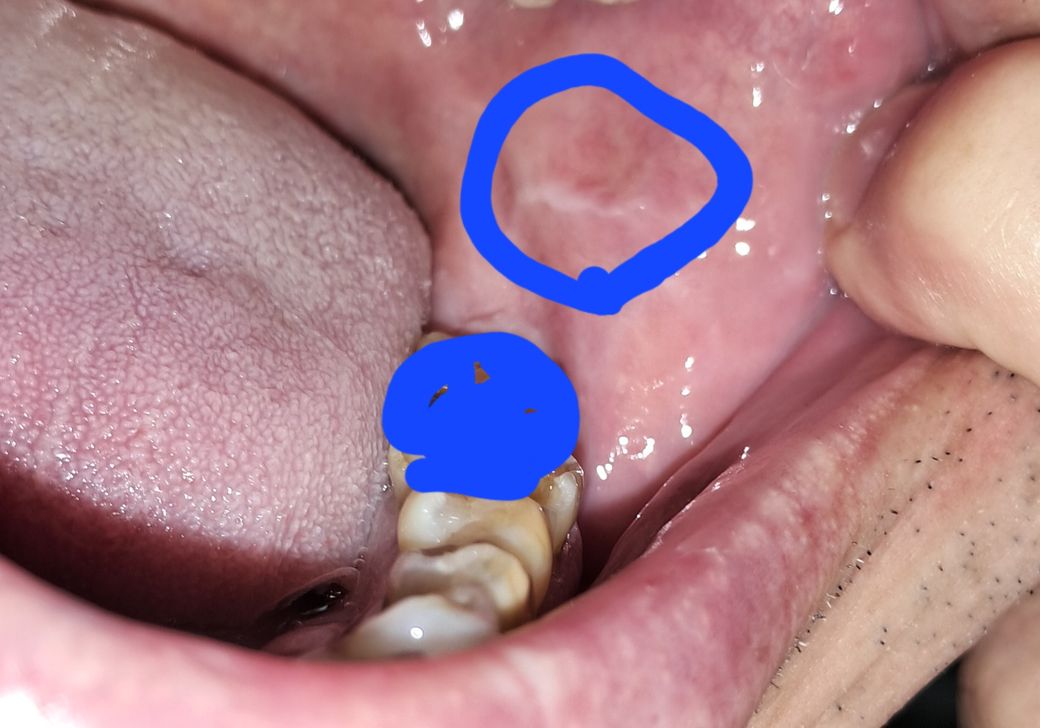

오른쪽볼 안입니다 한동안 불그스레한게 계속

이어지는데 왜 이런건가요? 아프지는 않습니다만 혹시 구강암이나 홍반증증상인가요?

올려주신 사진으로 보았을때는 악성이나 다른 이상 소견은 관찰되지 않습니다. 증상이 없다면 지켜보시기 바랍니다.